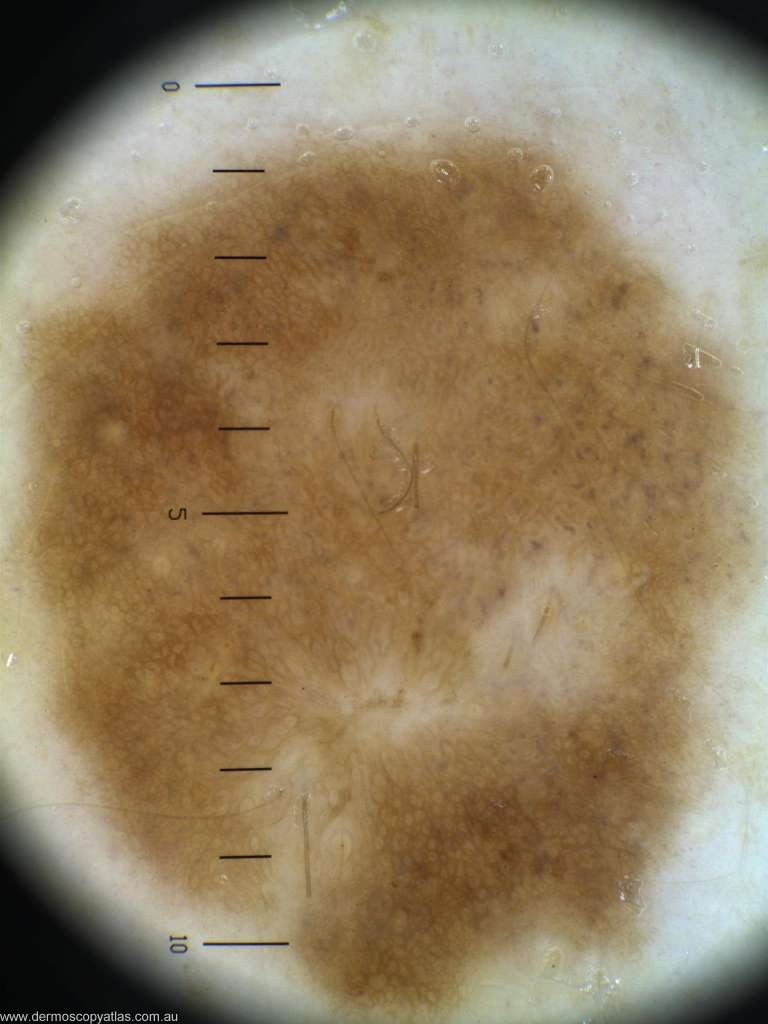

Case 8 Female age 50. Routine visit. No history.

Question: Which diagnosis is correct? Consider Melanoma in situ. Dysplastic nevus, LPLK, Solar lentigo and Compound nevus.

Answer: Histology: Compound naevus (no regression reported)